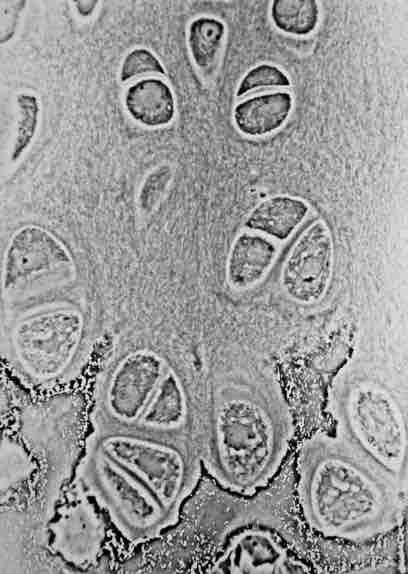

Hyaline cartilage showing chondrocytes and organelles, lacunae and matrix.